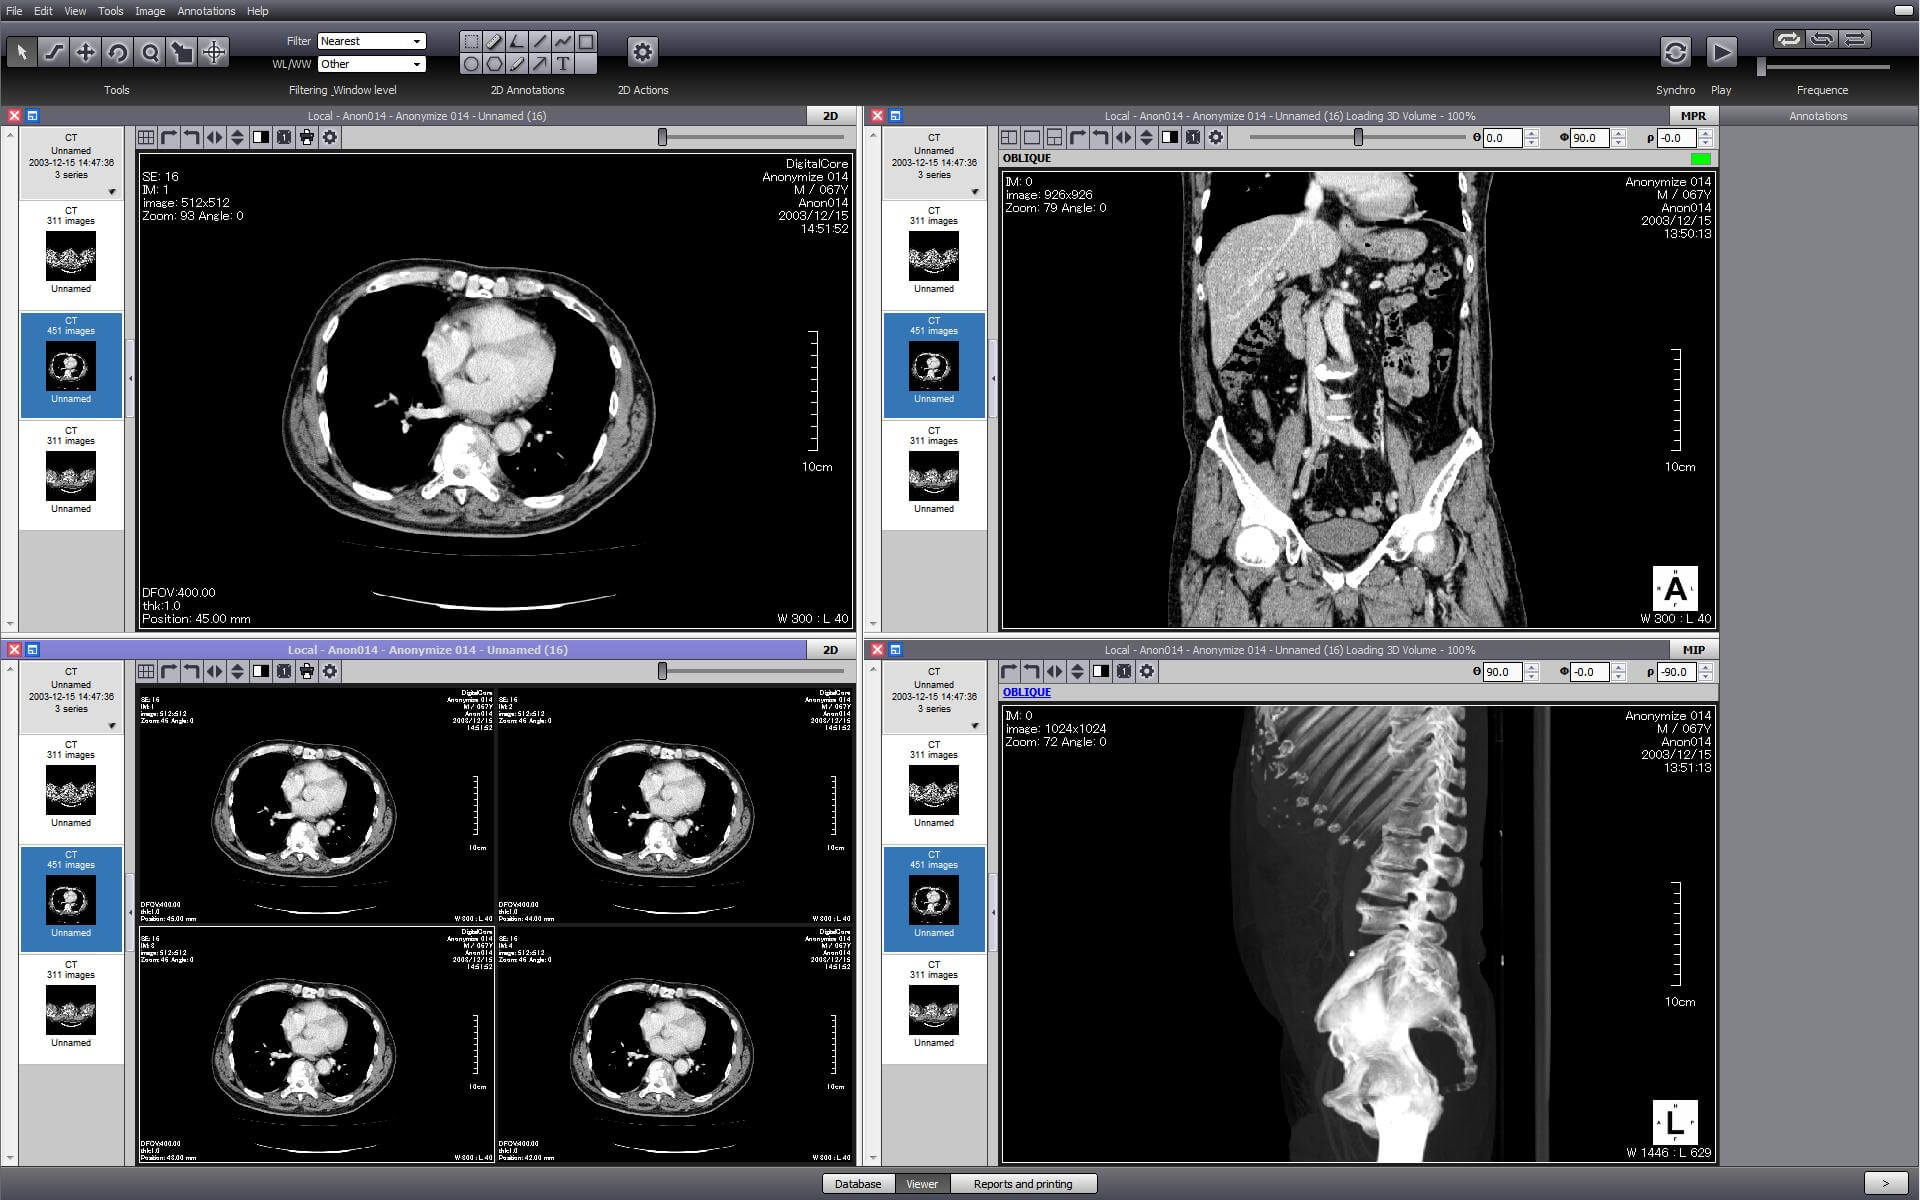

PostDICOM is one of the best DICOM viewers that offers almost all of the above features. It is compatible with Windows, Mac OS X, and Linux. It can be operated from android devices and iOS-based systems. PostDICOM comes with a cloud-based PACS, which allows you to access data from any device, anywhere, at any time. The viewer allows advanced image manipulation, such as 3D reconstruction, 3D volume rendering and MIP, and image fusion. It also offers an interface for creating reports, sharing files, and immediate uploading of all patient data to the cloud PACS.

The cloud-based PACS is unique to this software and offers several advantages. It allows researchers to upload relevant images on the PACS server for viewing, processing, and analyzing at various stages during the course of their clinical research. This ensures complete data integration and a smooth workflow.

Although paid subscriptions are available, the free trial version itself has several premium features. The cloud PACS offers free trial to its paid subscriptions, shares a month, and one or more user logins. These can be increased with different paid subscriptions. PostDICOM offers technical support for the free.